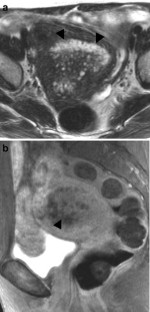

The endometrial cavity may demonstrate various imaging manifestations such as normal, reactive, inflammatory, and benign and malignant neoplasms. We evaluated usual and unusual magnetic resonance imaging (MRI) findings of the uterine endometrial cavity, and described the diagnostic clues to differential diagnoses. Surgically proven pathologies of the uterine endometrial cavity were evaluated retrospectively with pathologic correlation. The pathologies included benign endometrial neoplasms such as endometrial hyperplasia and polyp, malignant endometrial neoplasms such as endometrial carcinoma and carcinosarcoma, endometrial–myometrial neoplasm such as endometrial stromal sarcoma, pregnancy-related lesions in the endometrial cavity such as gestational trophoblastic diseases (hydatidiform mole, invasive mole and choriocarcinoma) and placental polyp, myometrial lesions simulating endometrial lesions such as submucosal leiomyoma and some adenomyosis, endometrial neoplasms simulating myometrial lesions such as adenomyomatous polyp and endometrial lesions arising in the hemicavity of a septate/bicornate uterus, and fluid collections in the uterine cavity (hydro/hemato/pyometra). It is important to recognize various imaging findings in these diseases, in order to make a correct preoperative diagnosis.

Fig. 3